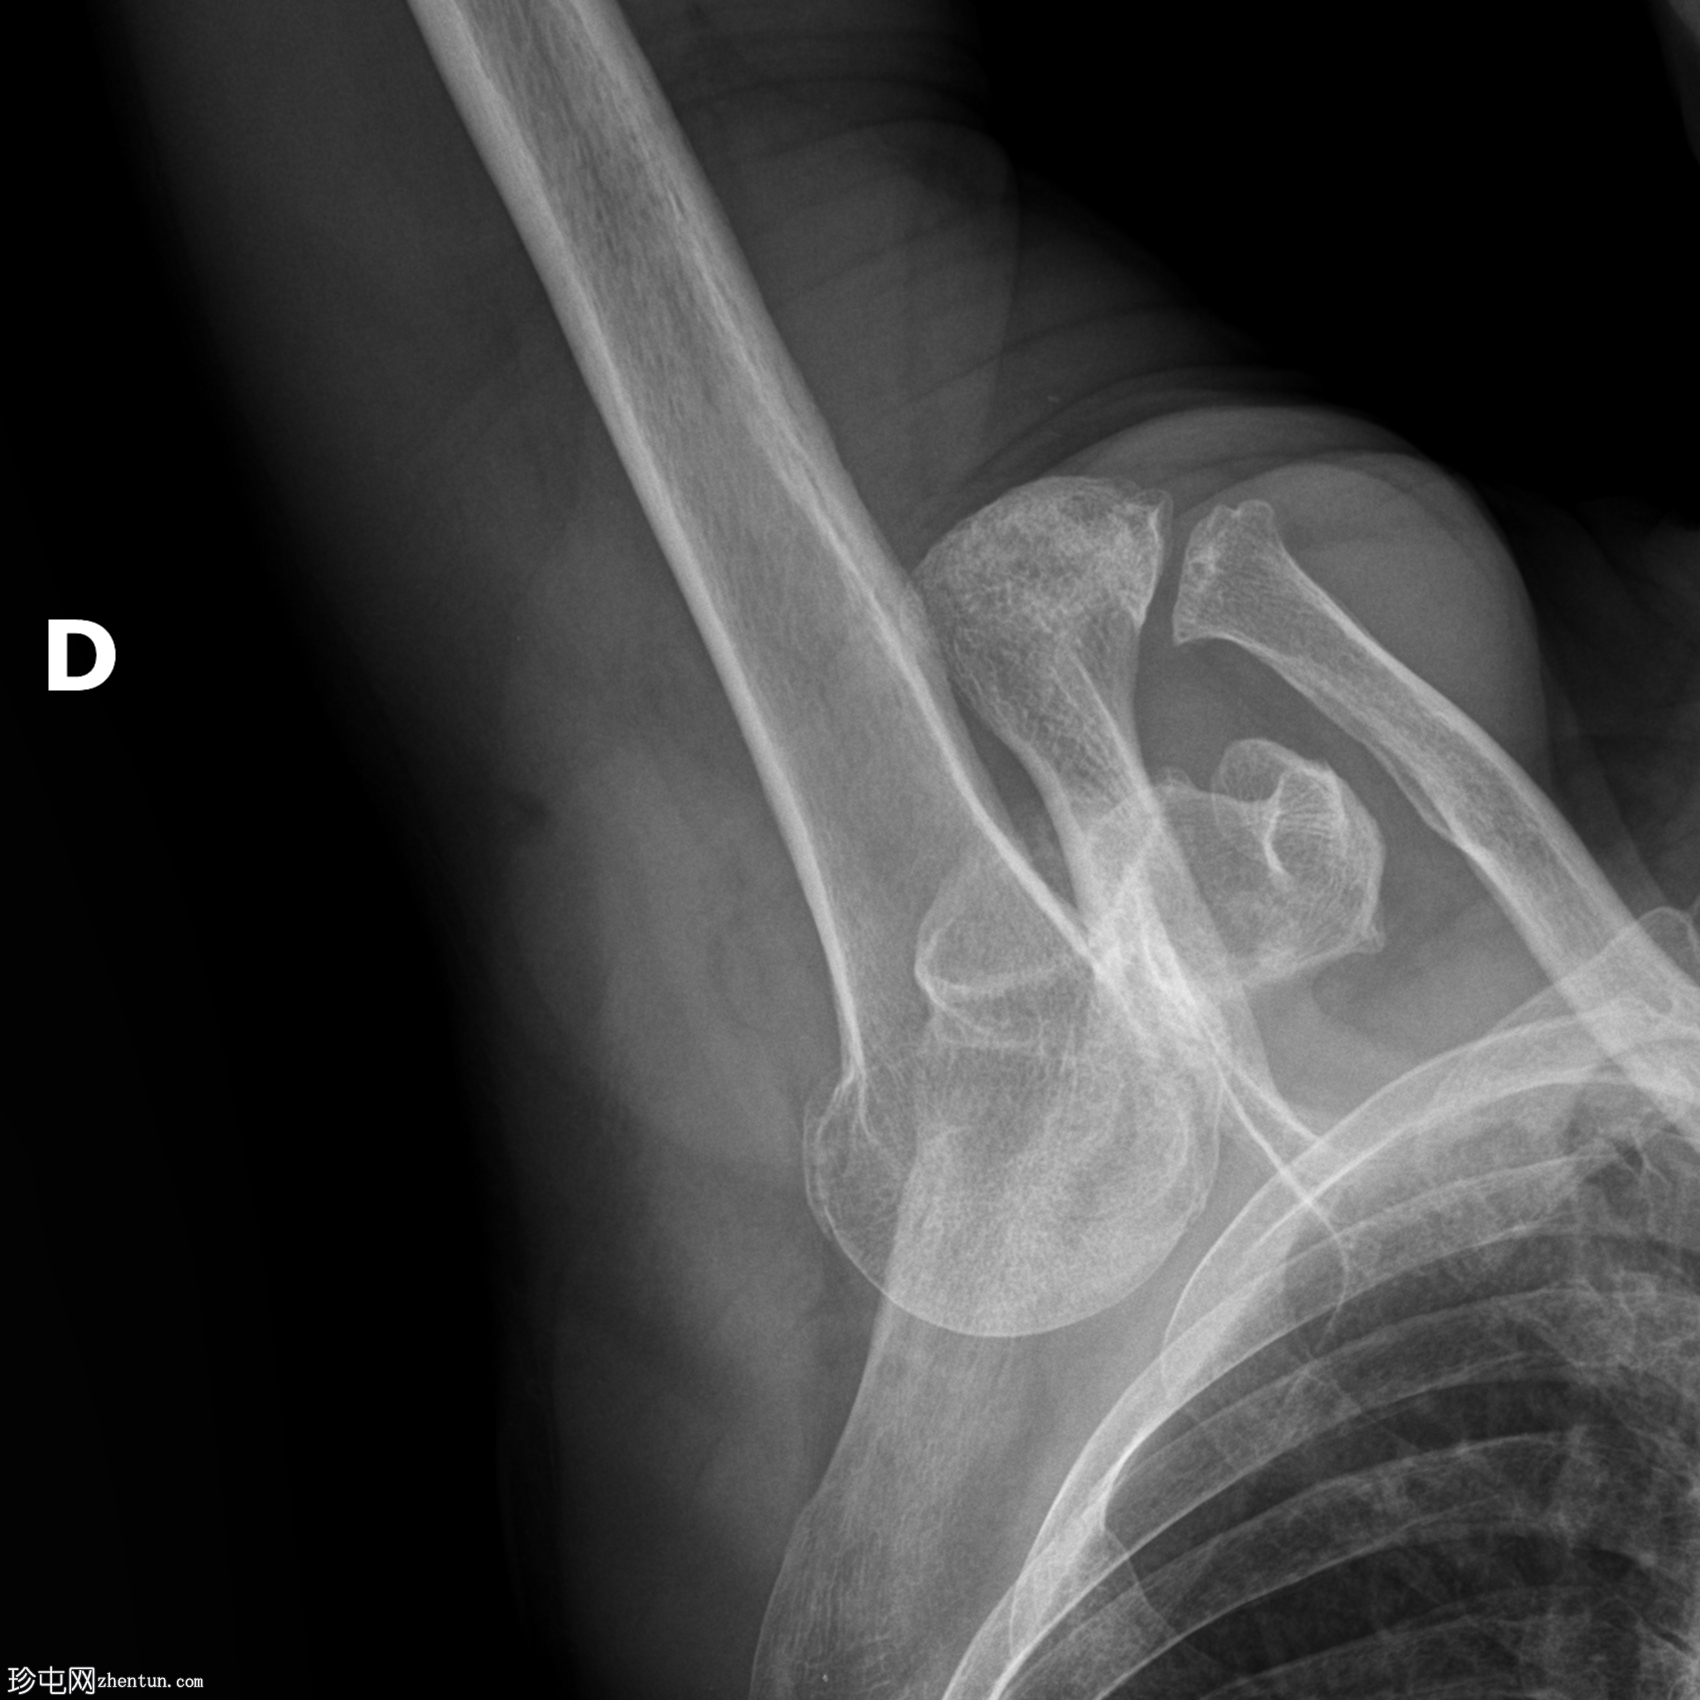

关节对位异常。

肱骨头向内侧和下方突出。手臂外展,肱骨干基本与肩胛冈平行。这提示肩关节下脱位。